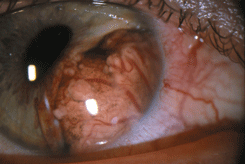

Опухоль чаще локализуется в области лимба. Растет медленно. Как правило, стелится по поверхности глазного яблока. Представлена ;папилломатозной ;и ;птеригоидной ;формами (см. рис. 12 на цветной вклейке). Значительно реже быстро растет в виде четко отграниченного узла (см. рис. 13 на цветной вклейке). Вокруг опухоли имеется ободок перифокальной инъекции сосудов. Резко расширены и эпибульбарные сосуды в зоне локализации новообразования. Возможно развитие ;пигментированной плоскоклеточной карциномы, которую следует дифференцировать с ;меланомой конъюнктивы. Пигментация опухоли обусловлена скоплением нормальных меланоцитов в ее строме. ;Пигментированный вариант плоскоклеточного рака ;чаще развивается у смуглых людей с темным цветом волос и не отличается бóльшей агрессивностью, чем ;беспигментная опухоль. Значительно реже развивается т.н. ;диффузная форма рака конъюнктивы с плоскостным ростом, которая может симулировать хронический конъюнктивит. Возможно прорастание опухолью склеры или роговицы и распространение вглубь глаза в область корнеосклеральных трабекул, радужки цилиарного тела, хориоидеи. В этих случаях рост опухоли приводит к развитию ;вторичной глаукомы, увеита, отслойки сетчатки. Рак пальпебральной конъюнктивы (т.е. конъюнктивы век) ;может сопровождаться искривлением хряща, укорочением сводов, птозом верхнего века. Эта форма опухоли имеет тенденцию через тарзо-орбитальную фасцию проникать в полость орбиты. Морфологическая картина характеризуется обширными полями акантоза, гиперкератоза, клеточным полиморфизмом, наличием элементов воспаления, обилием патологических митозов. Опухолевые клетки — мелкие, в виде веретен, с эозинофильной цитоплазмой и гиперхромным ядром.

Рисунок 12. Плоскоклеточный рак конъюнктивы и роговицы